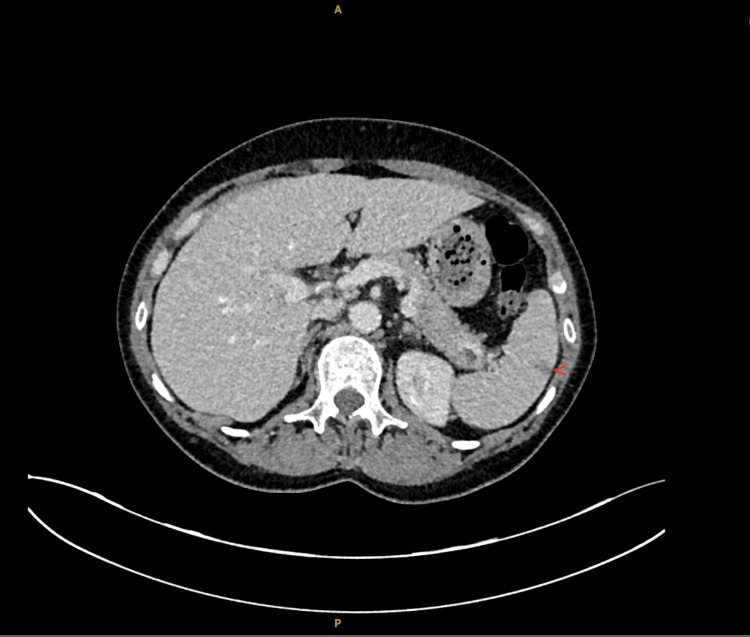

一个63岁的女性患者提出了急性医疗单位似乎是一个渐进的行动能力下降的情况下,一个常见的,往往非特异性的表现在急性医学。她描述了上肢和下肢无力和麻木影响了她的行走能力。最初,她的上肢麻木在社区治疗为尺神经压迫。她全年还多次出现呼吸短促,最初在社区中作为疑似哮喘加重加以处理;然而,她的症状是非特异性的。常规调查显示严重嗜酸性粒细胞增多(13.37 × 10⁹/L)、贫血和白细胞增多。神经生理学证实多发性单神经炎,进一步的自身免疫检测显示抗中性粒细胞胞浆抗体(P-ANCA)阳性和髓过氧化物酶(MPO)抗体升高。最终诊断为嗜酸性肉芽肿病合并多血管炎(EGPA),这是一种罕见的表现,挑战了最初的诊断假设。本病例是一个例子,说明并非所有EGPA的表现都是直截了当的,并且在急性医疗环境中可能会错过它。通过本病例报告,我们想强调 EGPA多发单神经炎的微妙和经常模糊的性质。我们还想强调延迟诊断对EGPA患者的影响,以及这如何影响患者的长期健康。最后,我们想讨论抗白细胞介素-5 (IL-5)靶向药物的新治疗方法,这些药物用于降低疾病的复发率。

A 63-year-old female patient presented to the acute medical unit with what appeared to be a case of progressive mobility decline, a common and often nonspecific presentation in acute medicine. She described upper and lower limb weakness and numbness affecting her ability to walk. Originally, her upper limb numbness was treated as ulnar nerve compression in the community. She also had multiple episodes of shortness of breath throughout the year, which were initially managed in the community as suspected asthma exacerbations; however, her symptoms were non-specific. Routine investigations revealed severe eosinophilia (13.37 × 10⁹/L), anaemia, and leucocytosis. Neurophysiology confirmed mononeuritis multiplex, and further autoimmune testing revealed positive anti-neutrophil cytoplasmic antibodies (P-ANCA) and elevated myeloperoxidase (MPO) antibodies. This was ultimately diagnosed as eosinophilic granulomatosis with polyangiitis (EGPA), a rare presentation that challenged initial diagnostic assumptions. This case is an example of how not all presentations of EGPA are straightforward and how it might be missed in an acute medical setting. Through this case report, we wanted to emphasise the subtle and often vague nature of mononeuritis multiplex in EGPA. We would also like to highlight the implications of a delayed diagnosis on patients with EGPA and how this affects the long-term health of patients. Lastly, we would like to discuss newer treatments with anti-interleukin-5 (IL-5) target drugs, which are used to reduce relapse rates in the disease.